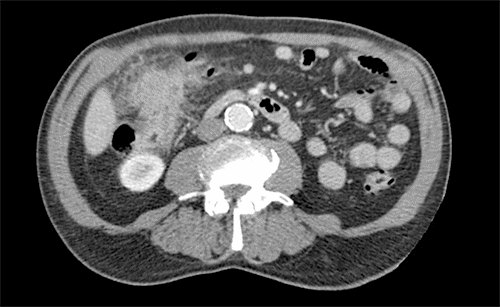

The patient was discussed at our multidisciplinary cancer conference (MDC), and the plan was to repeat the colonoscopy and CT scans. At that time, a repeat CT scan of the abdomen showed progression of the disease, with the mass now measuring 4.3 × 4.3 cm, abutting the inferior vena cava, with multiple enlarged mesenteric lymph nodes. Hepatic lesions concerning for metastases were also found (Figure 3 and Figure 4). Positron emission tomography (PET) scan showed hypermetabolic activity at the hepatic flexure, but PET could not differentiate between malignancy, inflammation, or infectious process. PET also showed nonspecific hypermetabolic liver foci. A repeat colonoscopy showed increased luminal edema, indicating a concerning advancement of the disease (Figure 5). Once again, multiple biopsies were taken, all negative for malignancy. Interventional radiology was consulted to perform a percutaneous biopsy of these new liver lesions; however, at the time of the procedure, no liver lesion was visualized, so a biopsy was not performed.

Figure 3. Second Abdominal CT Scan Showing Right-Sided Colonic Mass, Increasing in Size and Abutting IVC and Duodenum. Published with Permission

Figure 4. Coronal View of Second Abdominal CT Scan. Published with Permission

Right-sided colonic mass, increased in size, abutting the IVC and duodenum

Figure 5. Second Colonoscopy Showing Progression of Intraluminal Process. Published with Permission